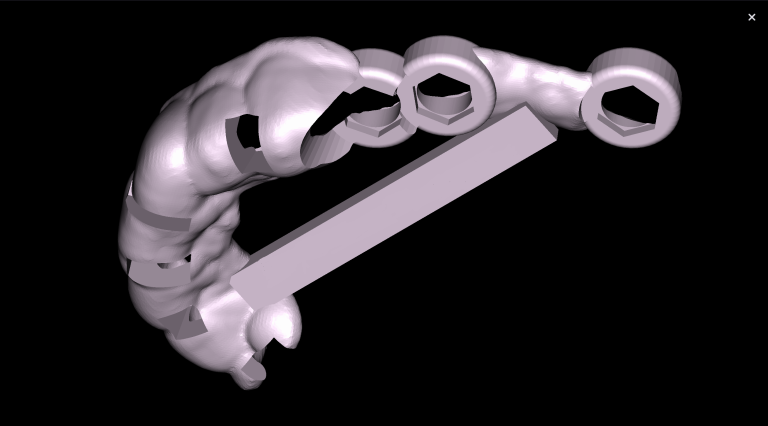

To plan implant treatment for the replacement of tooth 25 (Universal 13), the intraoral scanning data was uploaded into the STL module and obtain a 3D model for selecting the optimal spatial position of the implant and planning the virtual design of the template

Fully automatic segmentation and creation of 3D models from DICOM files allows you to select individual structures for printing models on a 3D printer

Based on these models, stereolithographic models were produced to plan the placement of the titanium mesh and ensure its accurate fit